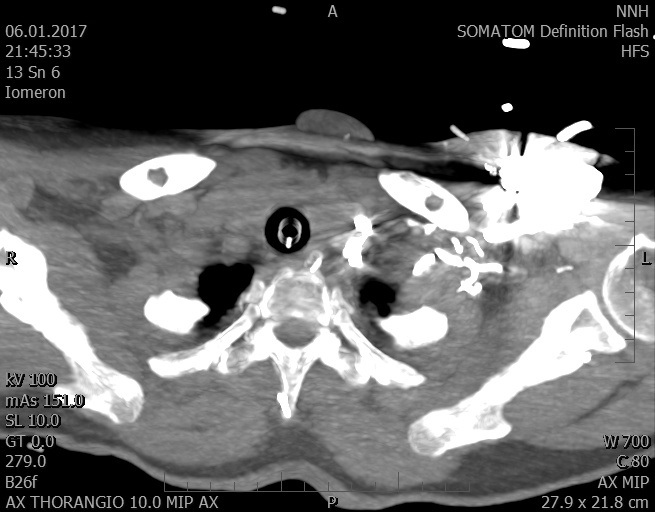

Video 2 - Echokardiograficky byla zjištěna těžká dysfunkce dilatační levé komory s nezvětšenou pravou komorou.Pro nejasnou příčinu zástavy jsme provedli i vyšetření výpočetní tomografií (CT), které vyloučilo plicní embolizaci (série 1 - soubory na konci článku). V den přijetí při přetrvávající oběhové nestabilitě byla nemocná opakovaně defibrilována pro fibrilaci komor se stabilizací rytmu po podání amiodaronu a mesocainu. Dle hemodynamických měření se jednalo o těžký kombinovaný šok. Vstupní laboratorní vyšetření bylo bez větších pozoruhodností. Posléze jsme doplnili anamnézu od příbuzných a zjistili, že pacientka užila do dvou hodin před srdeční zástavou první tabletu amoxicilinu na lehký respirační infekt. Při nevýtěžnosti vstupních vyšetření a nových anamnestických informacích jsme doplnili 14 hodin po kolapsu vyšetření koncentrace tryptázy v séru, která byla extrémně zvýšena (tabulka 2), což nás vedlo k podezření na anafylaxi.